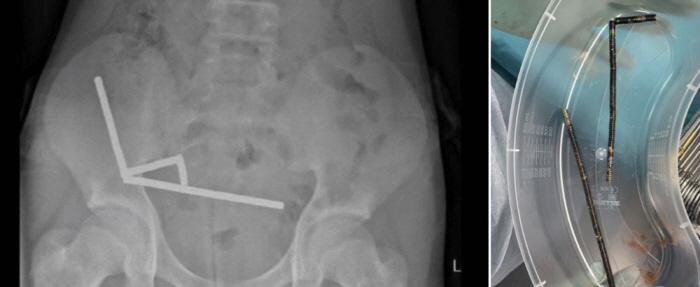

Abdominal x-rays showed that the magnets were attached to each other by magnetic force and distributed linearly in various parts of the organ, resulting in necrosis (tissue death) in the appendix, which is part of the small and large intestine.

The medical staff performed surgery to remove the intestine at the necrotic site along with the removal of the magnet, and the boy was discharged after 8 days of treatment. The date of the operation was not disclosed.